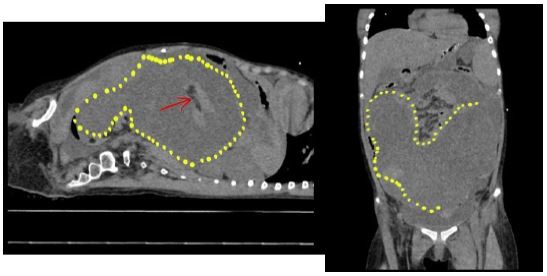

Figure 1: CT scan of the abdomen, demarcated lines showing hemoperitoneum.